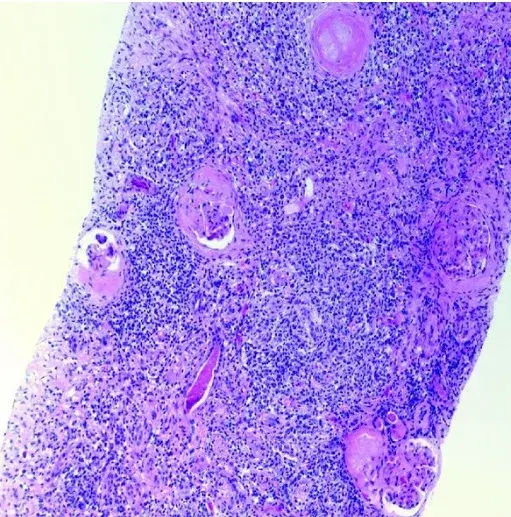

A microscopia de luz revelou glomérulos com lesões insudativas, hialinização arteriolar e proliferação mesangial (Figura 1A), mas **nenhuma** lesão ativa da nefrite lúpica foi identificada. A imunofluorescência mostrou **apenas** deposição linear de IgG ao longo da membrana basal glomerular com escassa deposição granular (Figura 1B). A microscopia eletrônica demonstrou apagamento do processo podocitário e espessamento da membrana basal.

Esses achados foram diagnósticos de **nefropatia diabética sobreposta a lesões crônicas de nefrite lúpica**.